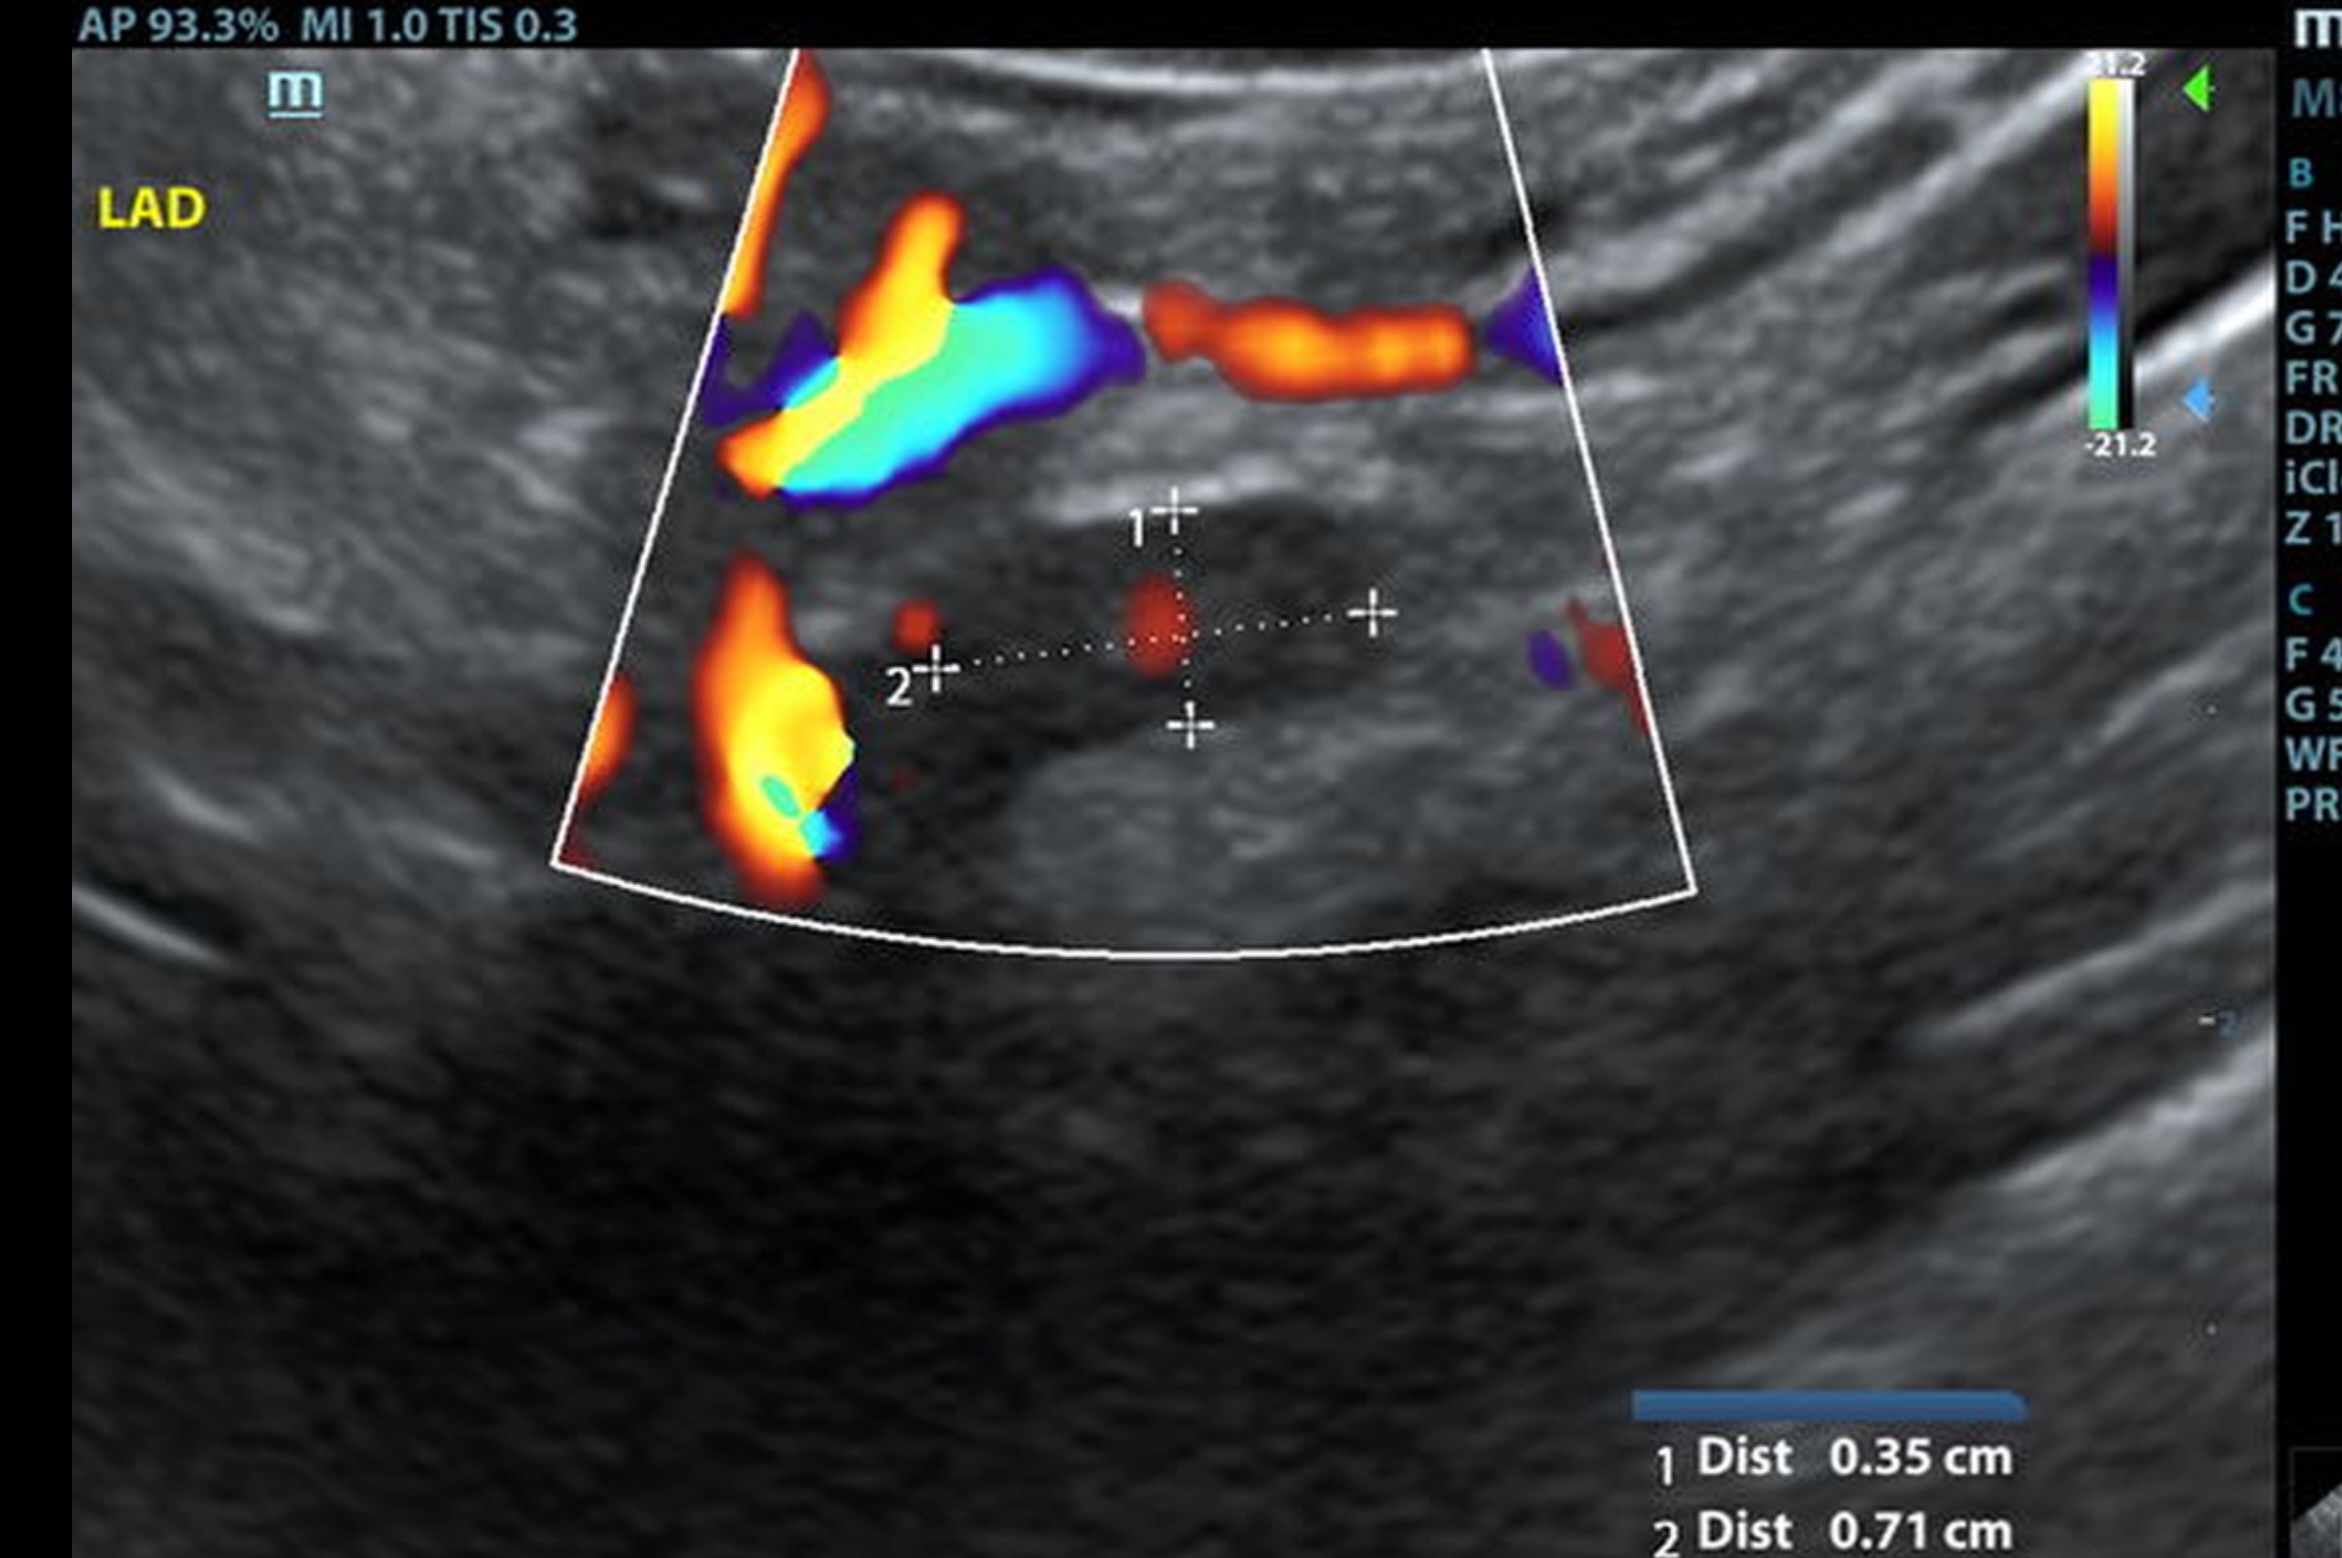

The left adrenal gland was visualized and recognized as normal for this breed. The left adrenal gland measured 0.7 c 0.35 cm. The region of the right adrenal gland revealed a mineralizing mass that impinged upon the vena cava and appeared to be occupying the phrenic vein; it measured 2.2 x 1.2 cm. This appears to be isolated. Normal right adrenal gland was not found.